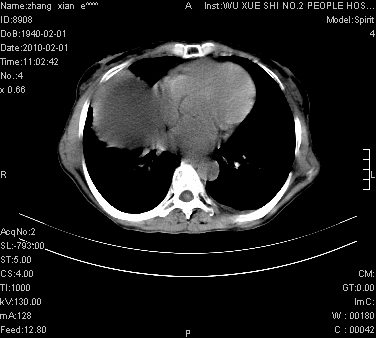

大量腹水,脾脏囊性占位,子宫颈占位,右侧腹股沟淋巴结肿大,建议+c,先查妇科。

腹盆腔大量积液,子宫增大,子宫颈增大外形不规则,内见低密度影,膀胱后壁显示不清,右腹股沟肿大淋巴结,脾脏囊性占位,子宫颈占位,子宫颈癌?建议增强。

腹盆腔大量积液,子宫增大,子宫颈增大外形不规则,内见低密度影,膀胱后壁显示不清,右腹股沟肿大淋巴结,脾脏囊性占位,子宫颈占位,子宫颈癌?建议增强。支持!

考虑:1、腹膜转移,大量腹水;2、脾占位性病变;3、左侧卵巢占位性病变,建议增强进一步检查。支持